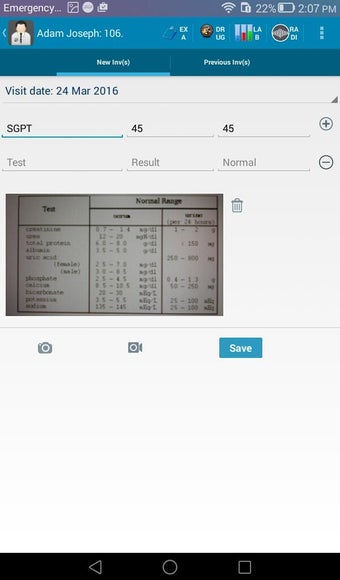

The Android Medical Records App by MedClin is a free medical records tracker app that allows users to store anamnesis, patient records, patient history, and health information. It is easy to use and provides numerous features such as username and password authentication, exporting medical data to Excel Sheet, and the ability to attach medical documents of any type. The app also has a smart search feature that allows users to search for patient information by name or ID, and even capture a photo for their profile.

In addition, the app has a blood pressure module that measures systolic, diastolic, and pulse, and allows users to export blood pressure reports to either PDF or graphs. The app also has a blood glucose (sugar) module that records blood sugar values and allows users to export blood glucose reports to either PDF or graphs. Users can also send blood pressure and blood sugar reports to their doctor. The app is compatible with multiple screens, including phones and tablets, and works on Chromebook systems. Overall, the Android Medical Records App is a great tool for patients and physicians alike for managing patient information and medical records.